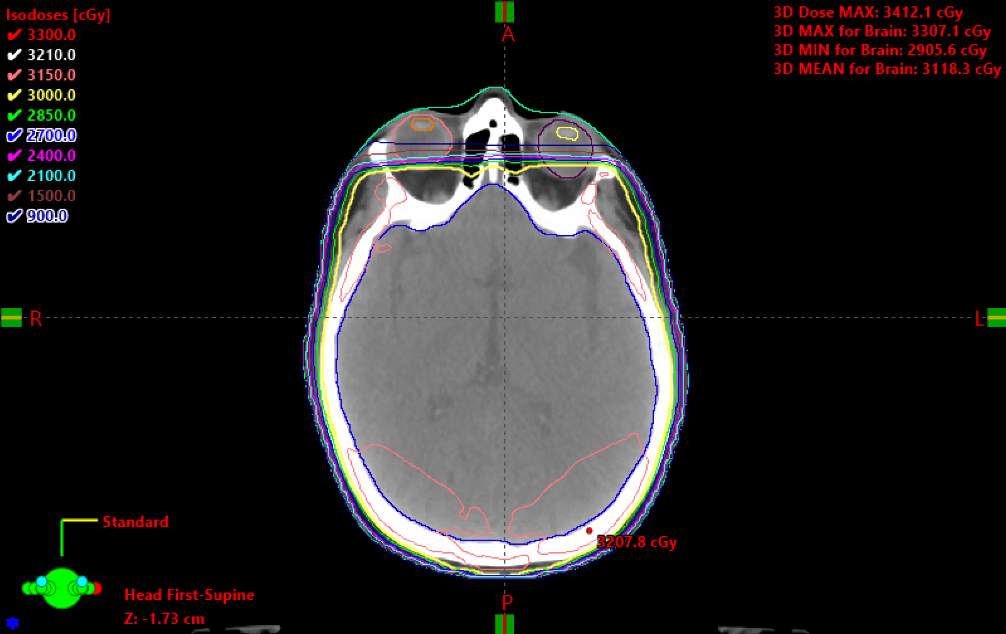

Field Blocking (Scalp Sparing)

A field with blocking to spare the scalp is shown above. The primary difference is that superiorly, the MLCs are adjusted to the outer table of the calvarium. This can help facilitate hair regrowth following WBRT.

Summary

With the setup complete, we will now create a plan similar to the one demonstrated.